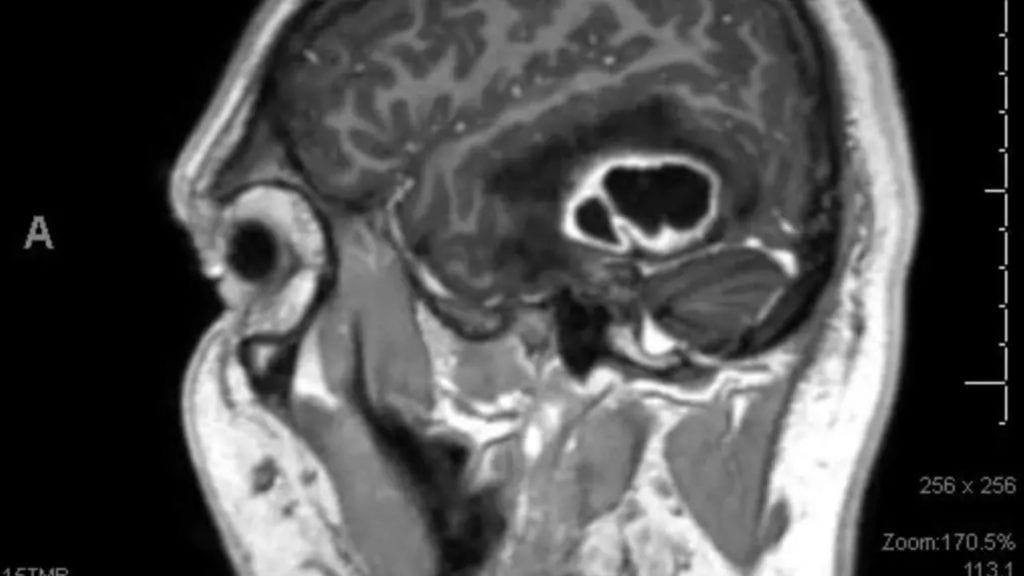

This patient with Trigeminal Neuralgia had surgery in 2012 by another surgeon at another institution. Initially, she felt well, but the pain gradually returned over…